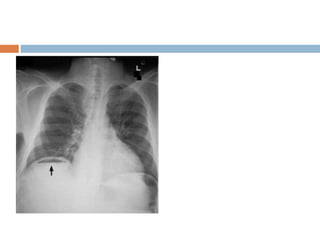

 This is chest radigraph , PA view with normal

exposure , no rotation and without any

apparent bony abnormality . Trachea is placed

centrally and lung fields are clear with normal

broncho- vescicular markings . Cardivascular

silhoutte is within normal limits with normal

cardiothoracic ratio. Mediastinum, costo

phrenic , cardio phrenic angles , dome of

diaphragm and soft tissue shadow within

normal limits .